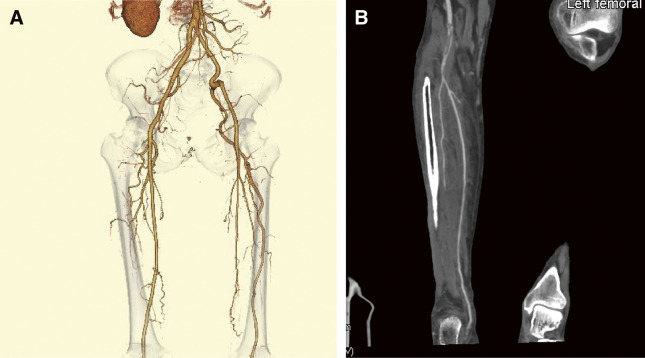

Persistent sciatic artery (PSA) is an exceptionally rare vascular condition that occurs in approximately 0.025%-0.04% of the general population. We describe the case of a 51-year-old man who presented with acute left lower limb pain and high fever. He was diagnosed with COVID-19 and isolated, and conservative treatment was performed for toe pain, resulting in left toe necrosis. Computed tomography revealed PSA occlusion in the left lower extremity. We diagnosed the patient with acute occlusion of the PSA due to COVID-19. The complicated disease was successfully treated using distal artery bypass.